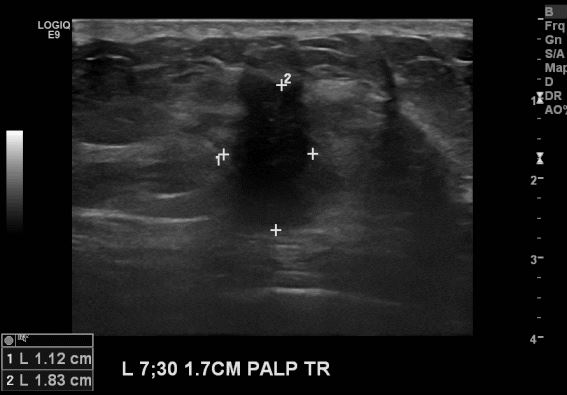

상기환자 좌측 유방에 만져지는 멍울로 내원하신 40대 여성분으로 좌측 7시 30분

방향에 만져지는 멍울 조직검사 시행하여 좌측 침윤성 유관암 진단되었습니다.